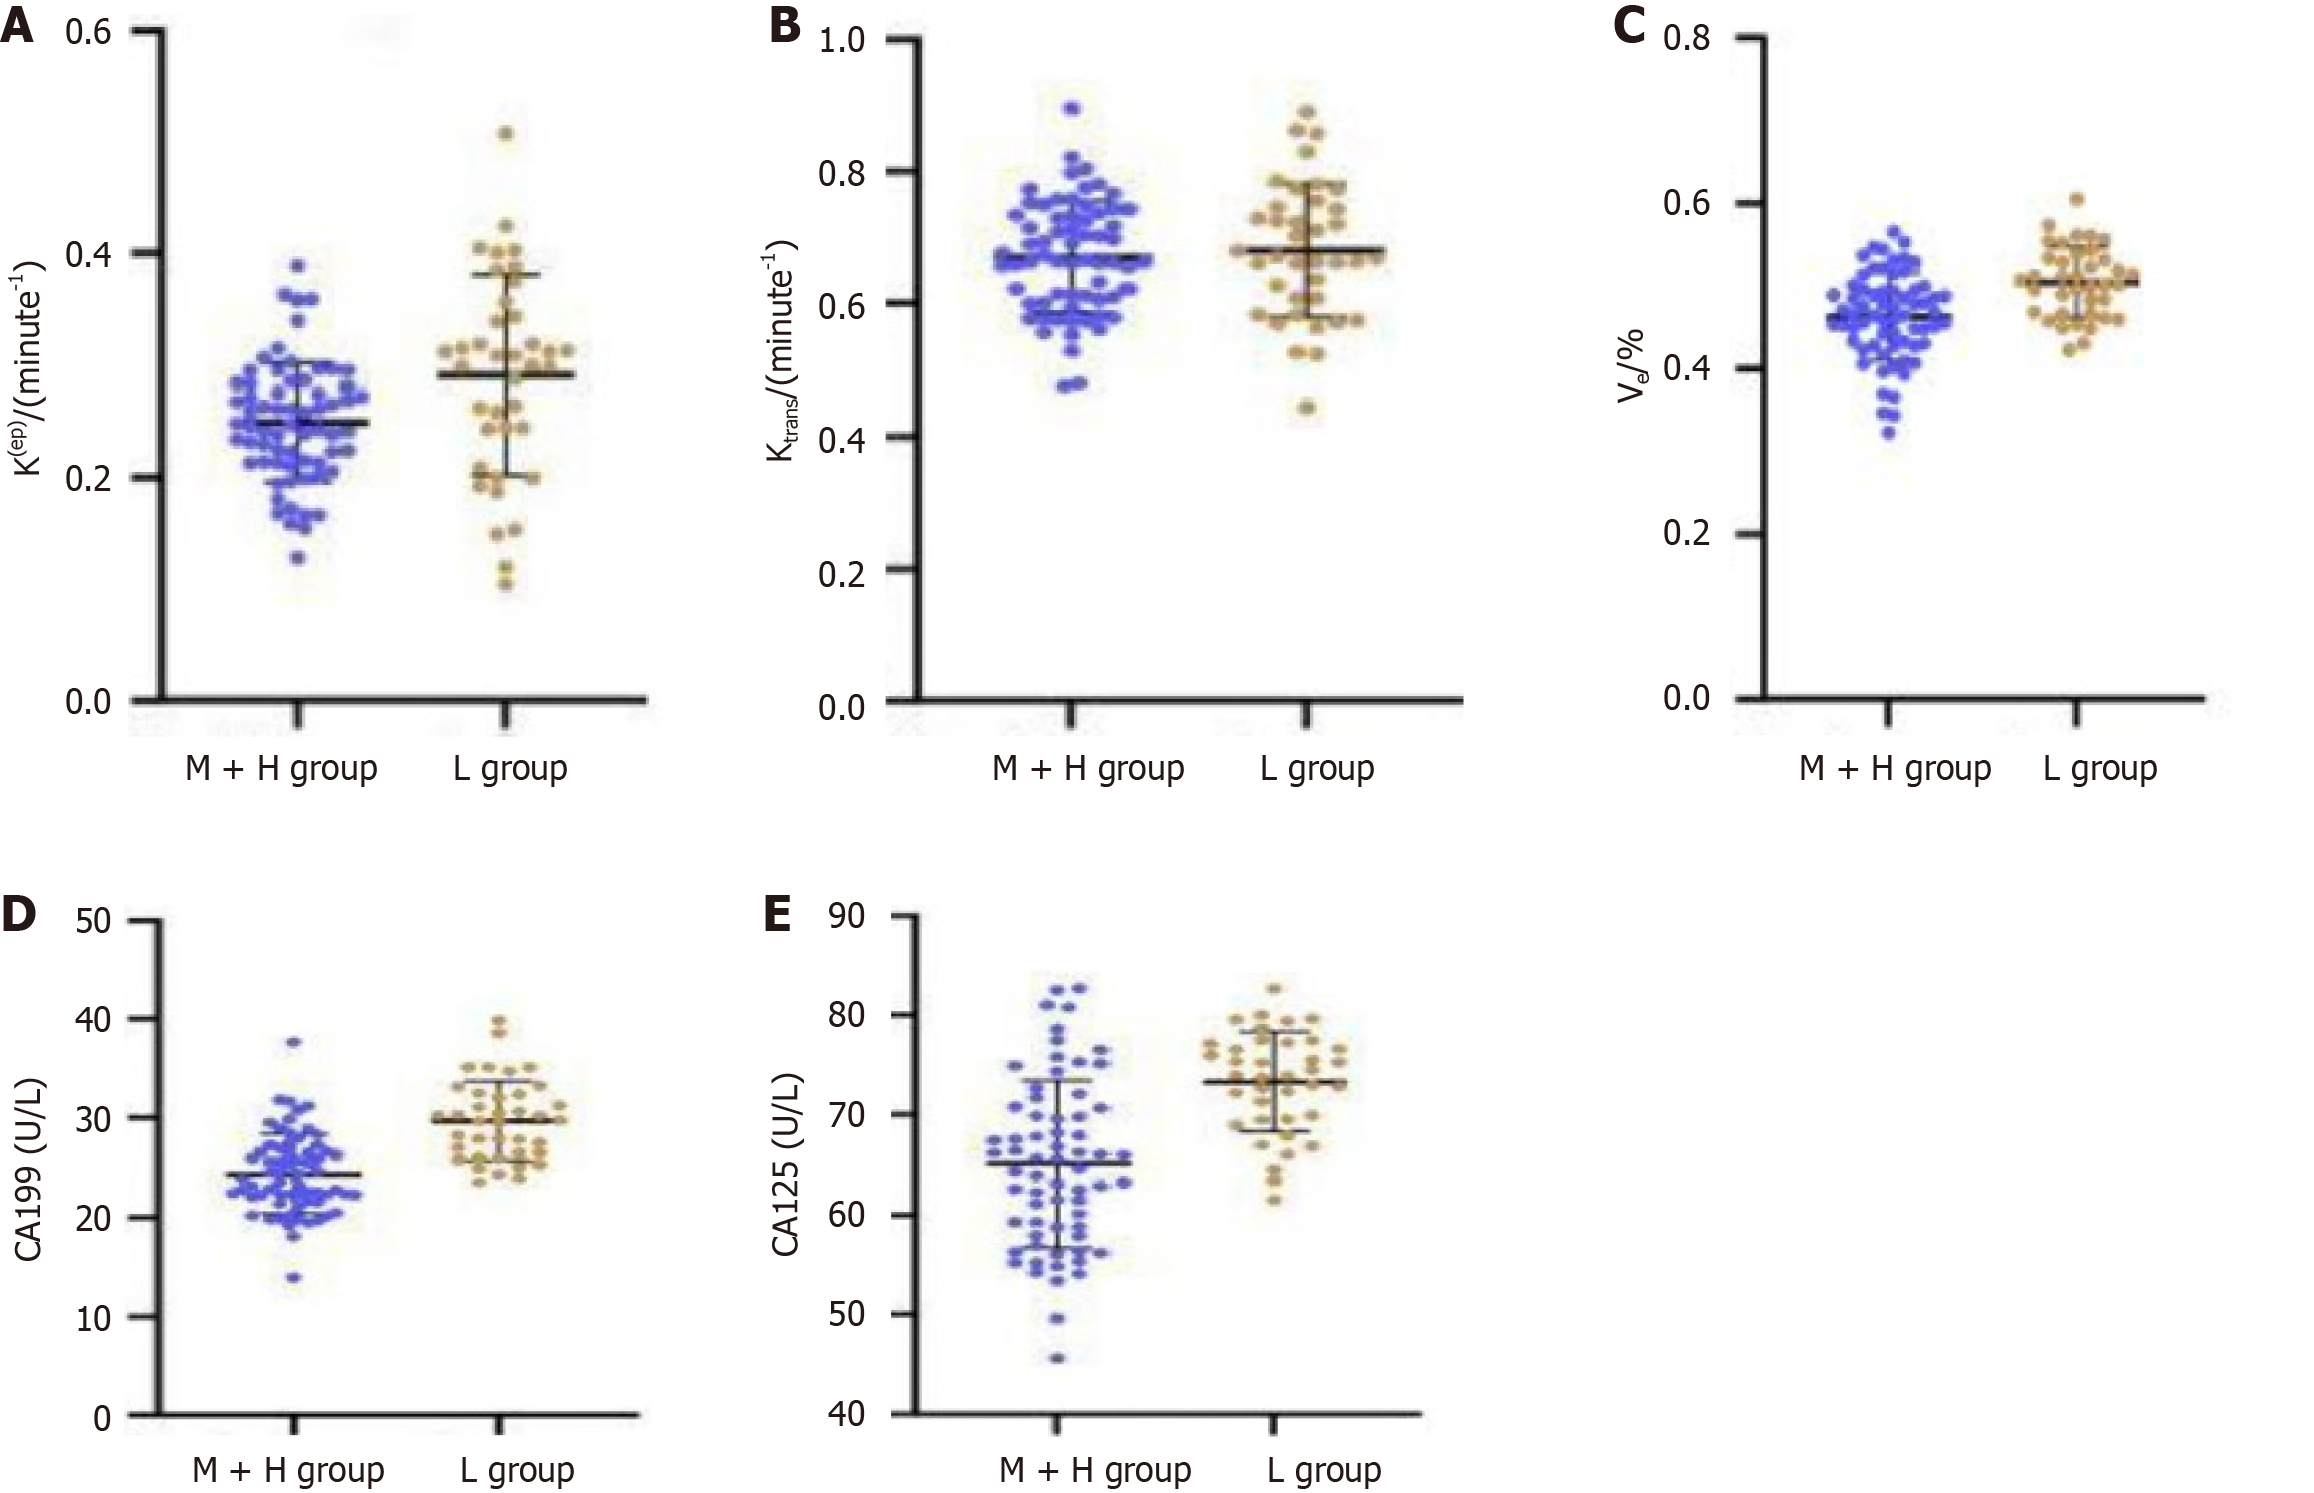

The findings presented in Figure 4 demonstrate that individuals with poorly differentiated rectal cancer exhibit significantly elevated Ktrans and Ve values compared to those with moderate to well-differentiated tumors (P < 0.05). Kep of the two differentiation groups had no difference (P > 0.05). In addition, serum levels of CA19-9 and CA125 are significantly elevated in the poorly differentiated group compared to moderately to well-differentiated group (P < 0.05). These findings suggest a potential relationship between DCE-MRI parameters and serum tumor markers with differentiation of rectal cancer.